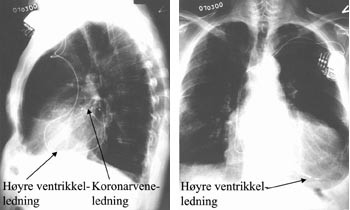

Terskelen for stimulering må kontrolleres også etter at introduserhylsen er fjernet og ledningen er fiksert, fordi ledningen lett kan dras ut av posisjon pga. den kraftige medstrømmen som er i sinus coronarius når man skal fjerne den 45 cm lange innføringshylsen. Deretter innføres en standard bipolar pacemakerledning via introduser i v. cephalica til apeks av høyre ventrikkel. Dersom pasienten har sinusrytme, innføres også en standard bipolar atriepacemakerledning via ny introduser i v. cephalica til høyre atriumsaurikkel (fig 2). Etter at høyre ventrikkel-ledningen er plassert, avledes elektrogrammet fra høyre ventrikkel og epikardialt fra venstre ventrikkel via pacemakerelektroden i kornarvenen simultant både på EKG-skriver og med pacingsystemanalysator (Medtronic analyzer 8090TM). Med skriverhastighet 100 mm/s måler man den interventrikulære ledningstiden ut fra elektrogrammene fra høyre ventrikkel og fra venstre ventrikkel (fig 3). Det bør være lengst mulig spredning i tid mellom ventriklenes spontane aktiveringselektrogrammer for at man ved pacing skal få best mulig resynkronisering av høyre og venstre ventrikkel. Tersklene for stimulering, P-bølgeamplituden og R-bølgeamplituden måles i henholdsvis høyre aurikkel og høyre ventrikkel med pacingsystemanalysator. Til slutt kobles alle ledningene til pulsgeneratoren InSyncTM som plasseres i pacemakerlommen.

Pasient 3 er en 76 år gammel mann med postinfarkt hjertesvikt (tab 1, 2). EKG viste sinusrytme og venstre grenblokk med QRS-bredde 180 ms (tab 3). Det ble implantert atriobiventrikulær pacemaker etter den angitte metoden (tab 3, 5, fig 2). Allerede første postoperative døgn angav pasienten at dette var første natten på lang tid han ikke våknet av dyspné.